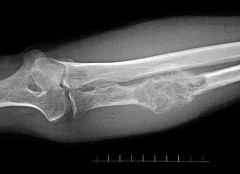

This is one of the rare presentations of the giant cell tumor of bone, a lesion that can be rather difficult to deal with even in its typical form. It is normally seen at the ends of the long bones and it is purely lytic (radiolucent) in most cases.

The above example is accompanied by secondary aneurysmal bone cyst and prominent periosteal new bone formation making a radiological diagnosis almost impossible. Microscopy (apart from the presence of too much osteoid) was typical, however.